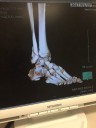

写真を上げますが グロテスクな写真もありますので ご了承ください。

1、2枚目 27日に骨折した直後の写真。

3枚目 3Dのレントゲン写真 クルクルまわすと360℃見えましたよ。

4,5枚目 手術後の写真です。